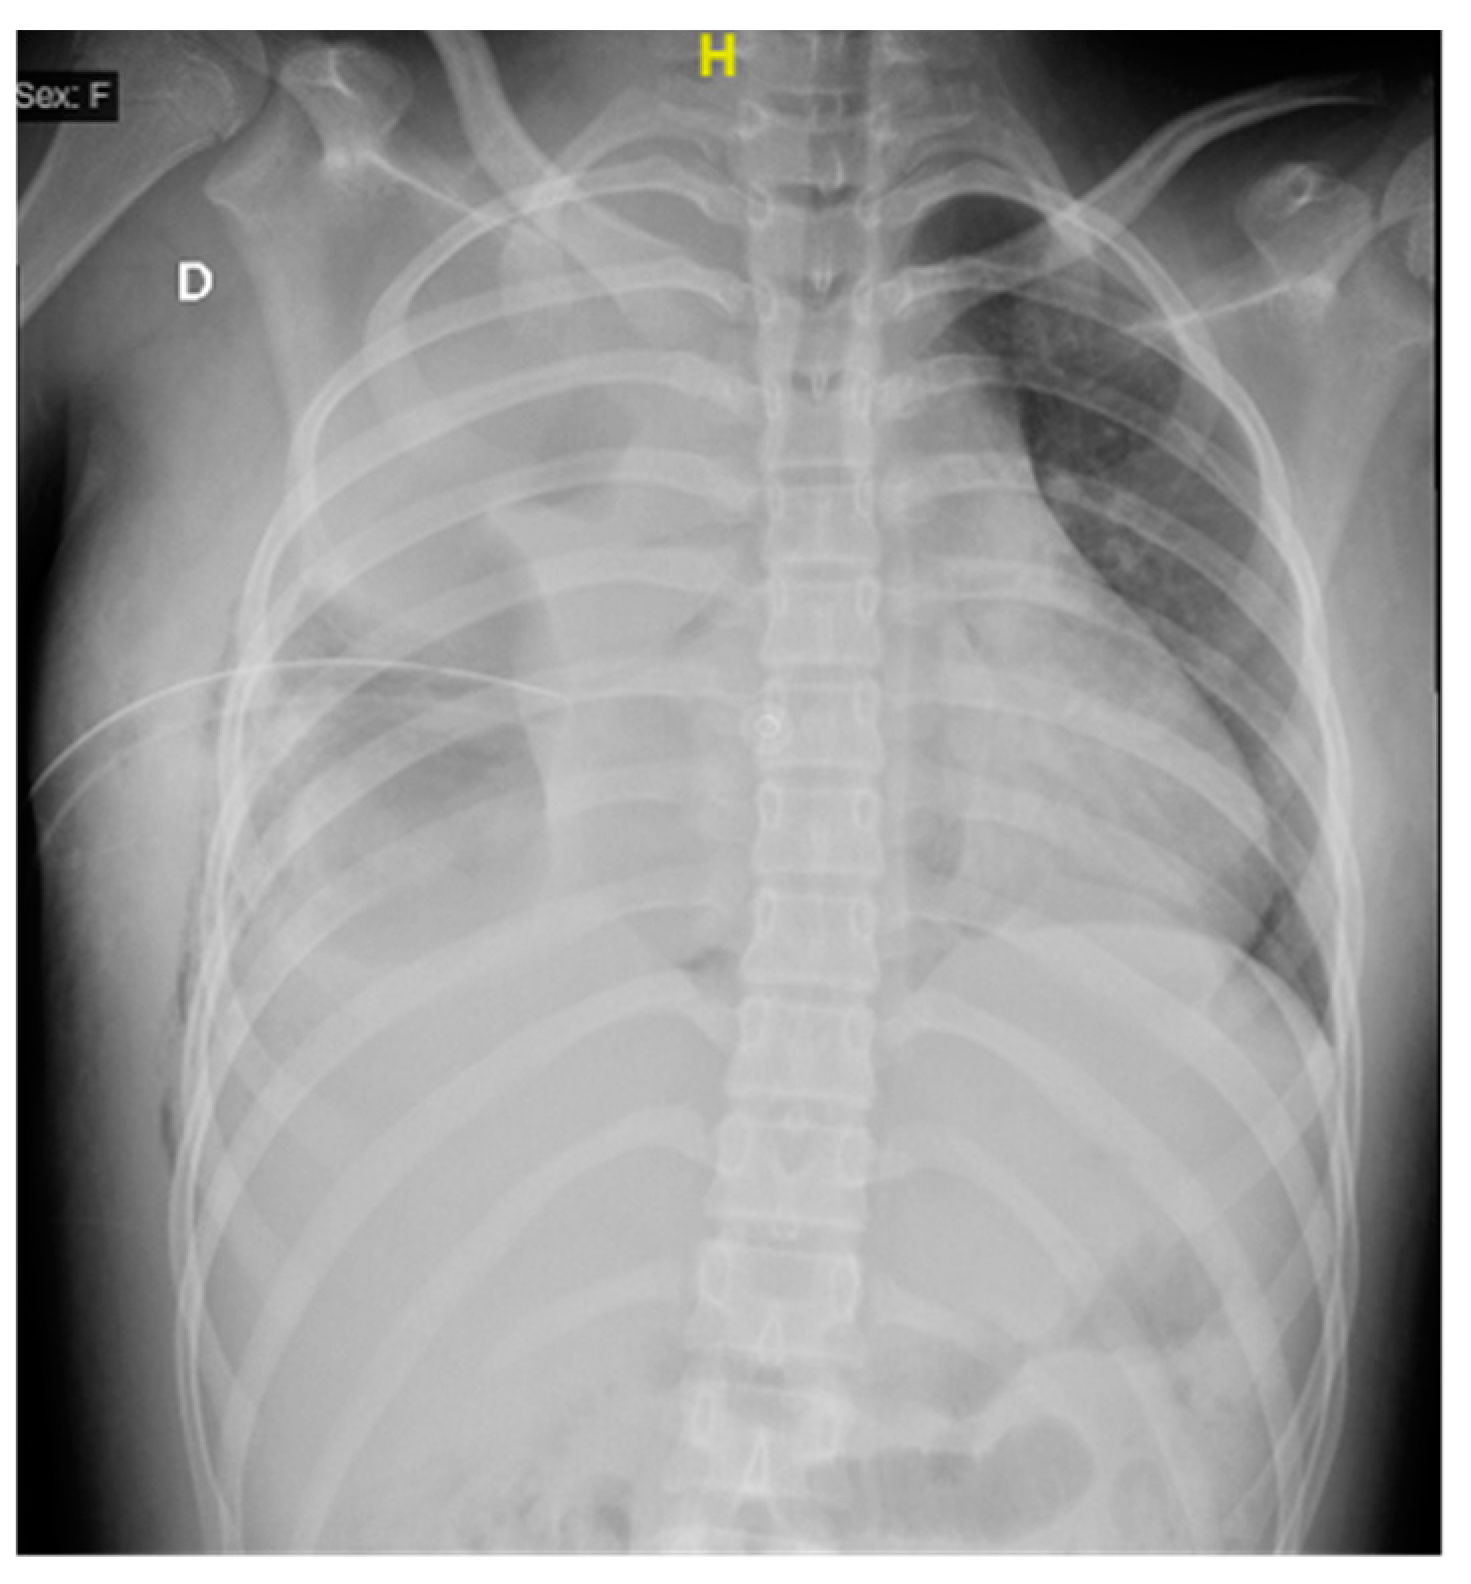

In the first 48 h after surgery, the patient continued to show data consistent with a systemic inflammatory response, with a vasopressor requirement and advanced airway management. Subsequently, due to the adequate evolution, a scheduled extubation was performed, and the patient was discharged from the intensive care unit five days after the procedure. On the following day, the thoracotomy surgical wound oozed purulent material, and wound dehiscence was noted around the endopleural tube (Figure 4).

Figure 4. Chest X-ray after surgery (72 h after), with the persistence of multiple alveolar consolidation zones, pleural drainage, and skin drainage.